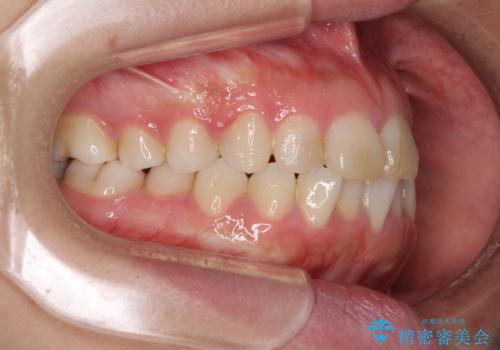

- ワイヤーではない矯正治療があると聞いたとのことで来院された患者様です。

長年前歯のデコボコを気にしていたもののワイヤー矯正に抵抗があり躊躇していたそうですが、インビザラインなら治療してみたいとのことで相談にいらっしゃいました。

インビザライン適用の歯列であったため、歯と歯の間を削るIPRを用いて改善することとしました。

お仕事柄、長時間のマウスピース装着が苦ではなかったので、歯列はすぐに整いましたが、ゆっくりとした交換頻度であったので、2年ほどの治療期間を要しました。